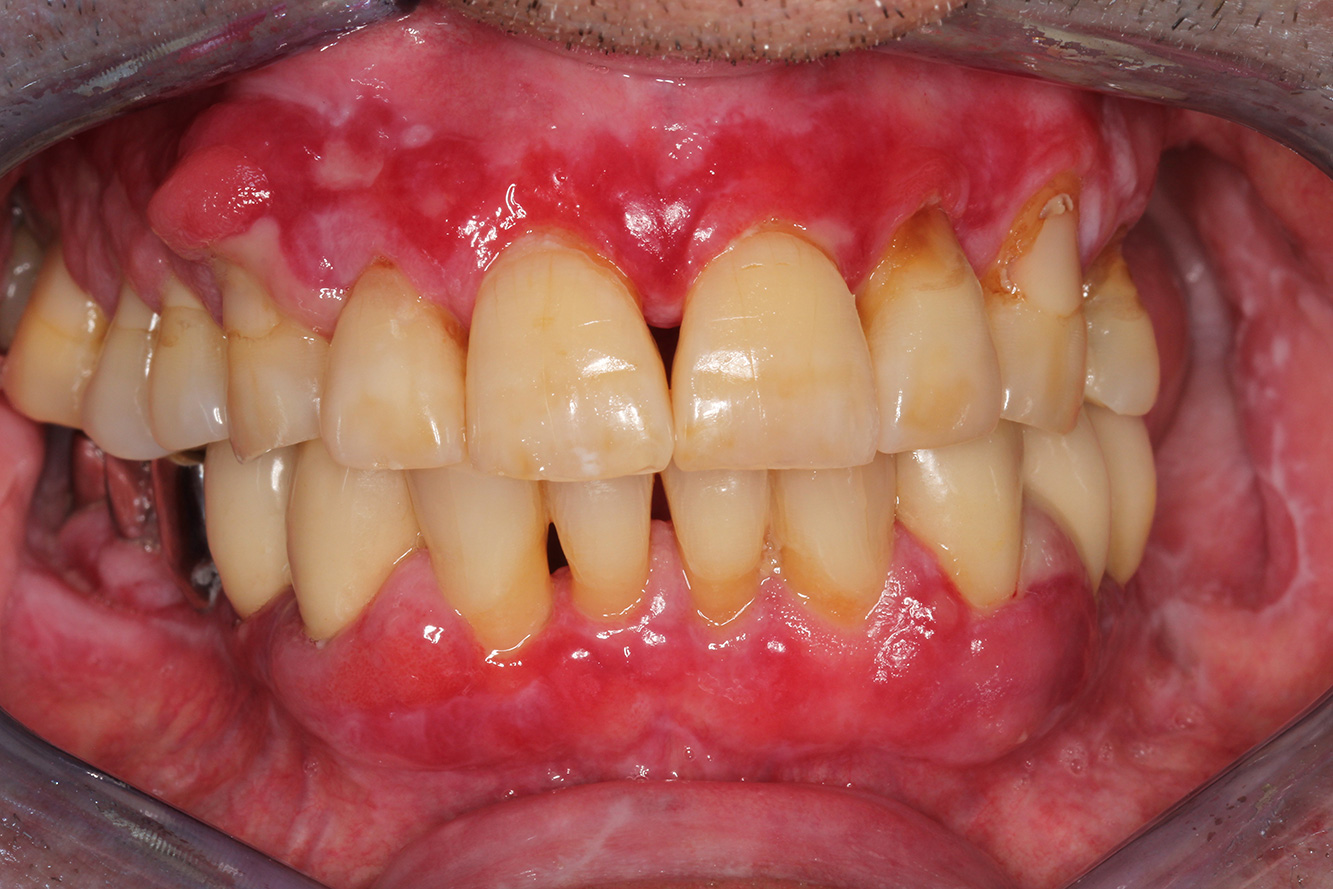

Casi di pazienti secondo l'IPCI seguenti studi di casi servono a mostrare l'interazione tra i fattori di bisogno e di rischio definiti per l'IPC così come gli effetti dei singoli fattori*. La paziente diabetica con una buona igiene oraleUna paziente diabetica di 51 anni con una buona igiene orale si presenta per una seduta di prevenzione. I valori di glicemia sono stabili con HbA1c = 6,2%, per cui si ritiene che la sua condizione possa essere sufficientemente gestita con la metformina (un farmaco per il trattamento del diabete). La paziente non presenta restauri esistenti o precedenti patologie orali. Sulla base dei referti disponibili si può constatare una gengivite nonostante una condizione altrimenti stabile. di più Case presentation: Complex Dental Prosthesis ManagementThe direct relationship between intraoral and general health, as well as the bidirectional influence that they may have on one another, is well-known (1,2). It is absolutely essential to consider both factors when planning preventive intraoral measures and treatment in the dental practice. The primary objective is the maintenance of patient health and quality of life from both dental and medical perspectives. more The (orally) healthy patient with implantsIn the medical history, the 55-year-old patient states that he has no systemic disease and is not taking any medication. The patient’s lifestyle is similarly unremarkable. The patient has a few tooth restorations and two implants (2nd and 4th quadrants). On the basis of current findings, gingivitis is identified in an otherwise stable periodontal condition on the reduced periodontium (stage III, grade A). more The healthy patient with pre-existing periodontal disease & peri-implantitisA 52-year-old patient presents at a preventive care session. The patient has no systemic disease and is not taking any medication. He has had various dental treatments and also has two active carious lesions. In addition, the patient has four implants (2nd, 3rd and 4th quadrants). He is revealed to have early periodontal disease (stage IV, grade B). His periodontal condition is stable; a probing depth of Probing depths (ST) of 5 mm is only evident at the implant in region 36. Gingivitis is also identified. more The Diabetic Patient with Pre-Existing PeriodontitisThis case report of a 52-year-old male with type 2 diabetes and periodontitis emphasizes personalized preventive measures and periodontal health maintenance to manage the moderate disease progression risk. more The 28-Year-Old Cigarette Smoker with Dental Erosions28-year-old patient, smoker, with erosions. The bidirectional relationship between oral and general medical health is very well known. It is no longer sufficient – and arguably even old-fashioned – to consider intraoral conditions in isolation. In order to create a personalized, case-specific preventive and patient profile, it is essential to take a detailed medical history and perform diligent examination of the general medical and intraoral health, as well as considering the two in combination. more Il paziente affetto da endocardite con lesioni cariose attiveIl paziente ha 39 anni e in passato è stato sottoposto ad un intervento per la sostituzione della valvola aortica dovuta a insufficienza valvolare ed endocardite. Assume regolarmente l'ASS 100 come anticoagulante. Per quel che riguarda lo stile di vita, il regime alimentare seguito dal paziente è classificato come “dieta che favorisce la formazione della carie”, per via del consumo regolare di cibi ad alto contenuto di zuccheri e dei sei-sette pasti consumati al giorno. La salute orale del paziente indica un rischio moderato di carie, con lesioni attive. Il rischio di parodontite è basso, tuttavia il paziente è affetto da gengivite. Si formulano quindi i seguenti consigli per il trattamento di profilassi. di più Il paziente trapiantato con iperplasia gengivaleSi presenta un paziente di 71 anni che ha subito un trapianto di reni e con anamnesi di ipertonia (ipertensione). Considerata la sua storia clinica, serve una terapia a lungo termine con ciclosporina che ha un effetto immunosoppressivo e amlodipina che è specifica contro l'ipertensione. Il paziente riporta anche gengive sensibili e sanguinanti. Per quanto riguarda invece lo stato di salute orale, il paziente ha un restauro, presenta un'iperplasia gengivale marcata, una parodontite allo stadio II, grado B con tasche attive e un'iniziale carie radicolare al dente 22 e in più mancano otto denti. Dalla valutazione del rischio di carie si evince un rischio moderato di carie (API 60). Per la seduta di profilassi si possono formulare i seguenti consigli per il trattamento. di più La paziente sana con precedente patologia parodontaleQuesta paziente di 68 anni non presenta alcuna patologia precedente né segue alcuna terapia che possano ritenersi rilevanti dal punto di vista odontoiatrico, e il suo stile di vita non comporta alcun rischio particolare. La paziente ha due impianti (3° quadrante, da cinque anni) e una precedente patologia parodontale (parodontite allo stadio IV, grado B) con perdita del dente. Al momento le condizioni parodontali sono stabili, tuttavia la parodontite aumenta in misura significativa le complicazioni biologiche degli impianti e c'è dunque il rischio di perdita dell'impianto (21). Per la seduta di profilassi si possono formulare quattro consigli. di più